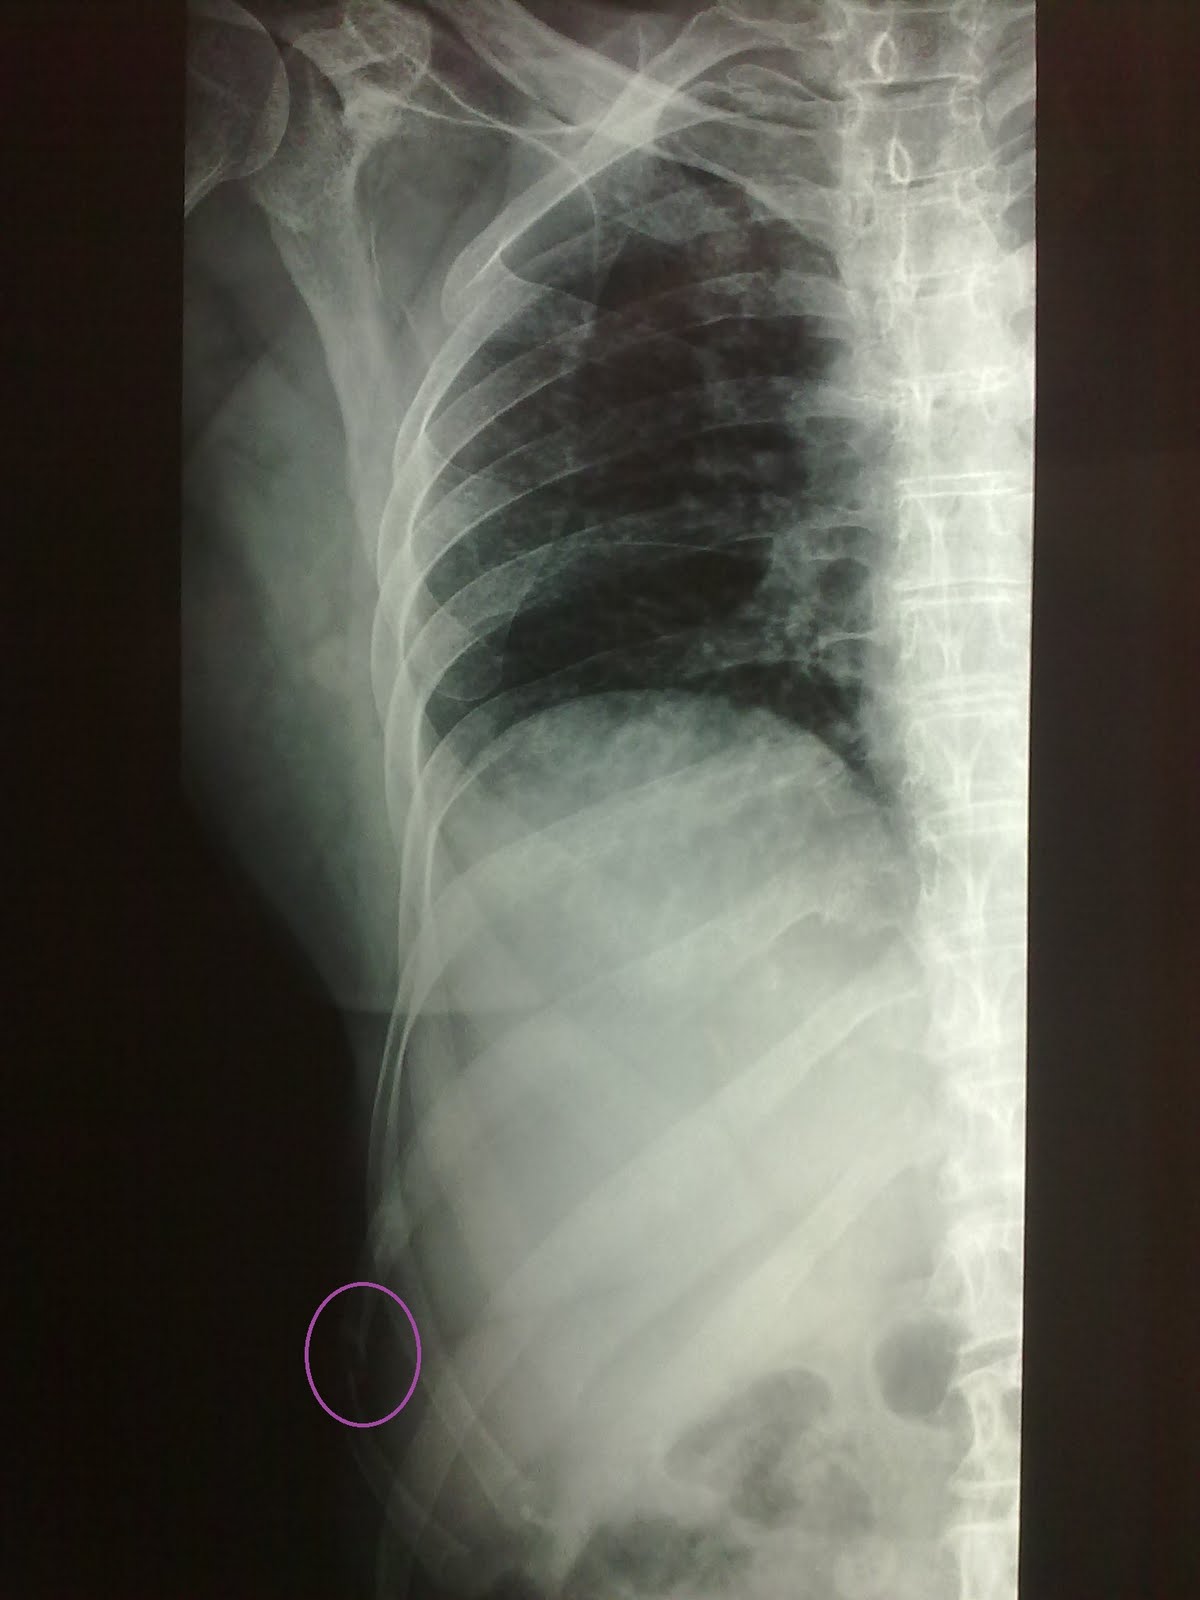

WebLa fractura de costilla es una lesión frecuente que ocurre cuando uno de los huesos largos de la caja torácica se quiebra o se fisura. Suelen verse afectadas por. WebA veces el fractura puede referirse varias costillas a la vez. Los mas a menudo afectados son los que se encuentran entre el 4 y el 10e costa. Esto se explica por el hecho de que. WebEl tiempo medio de recuperación por una fractura de costillas es de unos 60 días, normalmente no se requiere hospitalización, salvo circunstancias especiales. Las. WebSufrir una fractura de costilla en el trabajo significa que no podrá trabajar durante el tiempo que tarde en recuperarse de esta dolorosa lesión. Las costillas. WebLos trabajadores que enfermen o sufran una lesión deben solicitar su Baja laboral a través de su médico de familia. Pero no es lo mismo padecer una diarrea,. WebCuando hay una fractura de costilla el dolor es uno de los síntomas que puede convertirse en un problema cotidiano de la persona que lo padece, por eso seguir.

WebLas fracturas de costilla son un tipo de lesión que suelen producirse debido a accidentes de tráfico, traumatismos, golpes, así como a lesiones deportivas. También. WebDurante el examen físico, el médico presionará suavemente las costillas. También podría escuchar los pulmones y ver cómo se mueve la caja torácica mientras. WebEl mayor riesgo de esta lesión en la zona costal es la perforación de los pulmones, el corazón o la arteria principal (aorta) por la costilla rota. Esto puede provocar hemorragia.